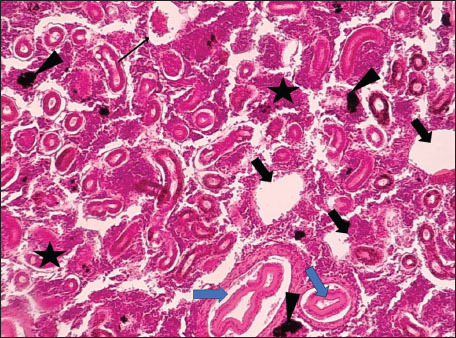

Histopathological examination of the kidney tissues of L. sceleratus revealed multiple alterations. Prominent melanomacrophage centers (MMCs), necrotic areas, dilatation of Bowman’s capsules, and vacuolar degeneration were observed (Fig. 1), associated with interstitial lymphohematopoietic tissue (Fig. 2). Dilated and congested blood vessels and extensive MMCs were also noted (Fig. 3). Renal degeneration surrounding lymphohematopoietic tissue, large clusters of MMCs, and thickened, congested vessel walls within fibrotic areas were evident (Fig. 4). Atrophic renal degeneration with necrotic and vacuolar changes was observed (Fig. 5). Severe inflammatory infiltration of lymphatic cells and granulomas with necrotic centers, surrounded by fibrous tissue, was detected (Figs. 67).

Fig. 5. Histopathology of the kidney in an adult L. sceleratus showing atrophic renal degeneration (thick arrows), necrotic tissue (stars), and vacuolar degeneration (thin arrow). ×400 H&E.

Moderate tubular degeneration and Bowman’s capsule dilatation were recorded, whereas MMC proliferation was severe (+++). Vascular congestion and mild inflammation were observed. No parasitic structures were detected in kidney tissues. Observed alterations represent descriptive baseline histopathological changes.

The present study revealed pronounced histopathological alterations in both the kidneys and gills of L. sceleratus collected along the Libyan coast. Kidney lesions, including tubular degeneration, Bowman’s capsule dilatation, proliferation of MMCs, vascular congestion, and inflammatory infiltration, were associated with histologically detected structures, but no parasitic structures were detected in kidney tissues. These patterns are commonly reported in marine teleosts exposed to chronic environmental stressors (Ali et al., 2014; Steinel and Bolnick, 2017; Carreras-Colom et al., 2022). These lesions should be interpreted as descriptive indicators of physiological stress rather than direct evidence of chemical pollution or causality, consistent with Flores-Lopes and Thomaz (2011). Vascular abnormalities, including congestion and thickened vessel walls, were evident, which may reflect chronic circulatory disturbances or inflammatory responses rather than acute toxicity (Bernet et al., 1999; Thophon et al., 2003). Interstitial lymphohematopoietic tissue, inflammatory cell infiltration, and granulomatous formations suggest that parasitic or microbial challenges could contribute to renal lesions. Despite these histopathological changes, the sampled fish appeared healthy at capture, demonstrating the potential physiological resilience of marine teleosts. Fish kidneys possess compensatory mechanisms, and gills serve critical osmoregulatory and excretory functions, allowing survival despite structural alterations (Evans et al., 2005; Hwang et al., 2011; Hinton et al., 2018; Leone et al., 2018). Gradual development of renal lesions likely enables adaptation without acute organ failure.